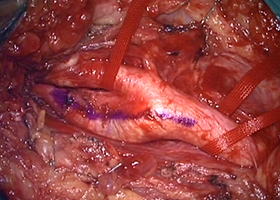

② 頚動脈狭窄症

脳梗塞の原因となる頚動脈狭窄症に対して内膜剥離術を行います。

56歳男性、左半身麻痺で発症しました。

[術前画像所見]

右側で頸部内頚動脈が細くなっているため右脳に脳梗塞を生じた患者様です。

[手術所見]

手術で血管の内部で肥厚した内膜を除去します(内膜剥離術)。

-

右頚動脈の露出 -

内部に充満したプラーク -

プラーク除去 -

血管壁縫合

[術後画像所見]

術後造影CT -

術後MRI拡散強調画像

頸部狭窄は解消しており、新たな脳梗塞など生じていません。